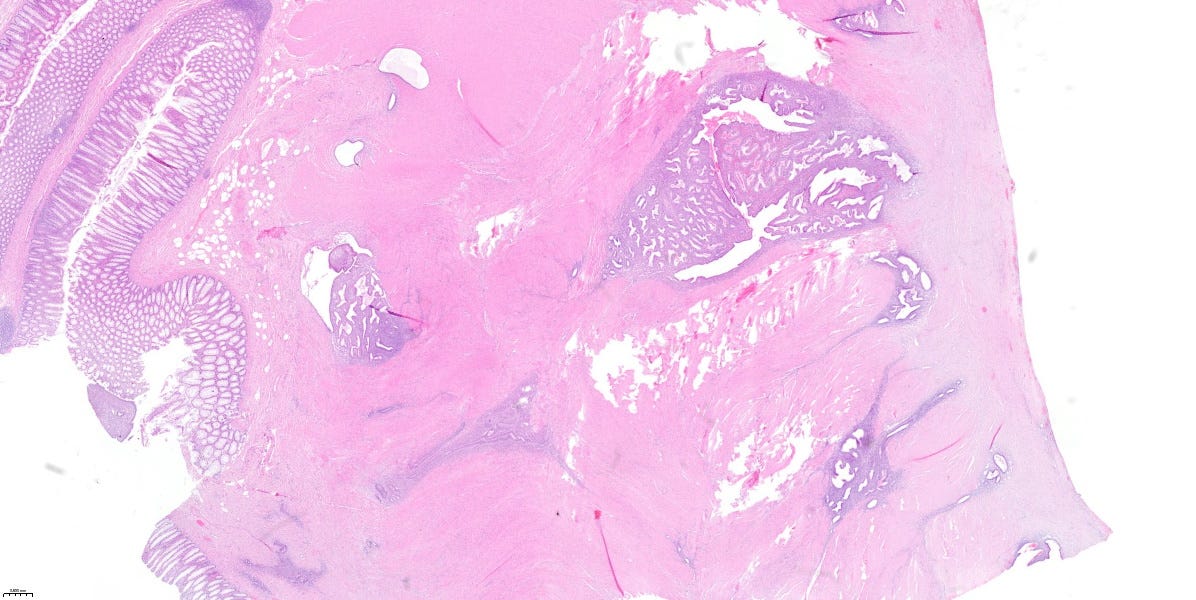

Kazuistika mesiaca

📝 Tento prípad mi „pristál” na stole počas tvorby tohto newslettera (úroveň 2/5). Karma predsa len existuje. 🙂

Resekát časti hrubého čreva 38-ročnej ženy, s mnohopočetnými suspektnými ložiskami v jej stene a pod viscerálnym peritoneom, ktoré boli viditeľné voľným okom.

✅ D. Endometrióza hrubého čreva.

💡 Endometrióza je prítomnosť „ostrovčekov” histologicky normálneho endometria v iných tkanivách a orgánoch než je výstelka (sliznica) dutiny maternice.

V ektopických lokalitách podliehajú endometriálne žliazky a stróma rovnako hormonálnym zmenám ako v dutine maternice.

V dôsledku toho vznikajú ložiská krvácania, ktoré sa postupne organizujú, neskôr peritoneálne zrasty v prípade GIT-u, atď. Klinický obraz je preto rôznorodý, v závislosti od lokality postihnutého tkaniva.